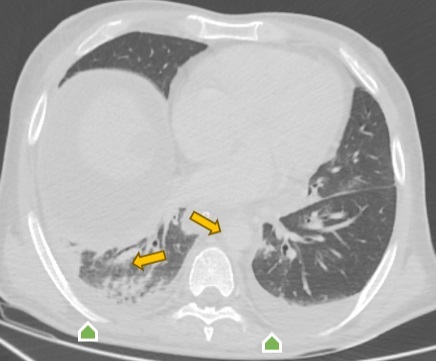

Во время проведения полихимиотерапии по установленному протоколу у пациента отмечались цитопения, гипокоагуляция, нарушения электролитного баланса и увеличение показателей острой фазы воспаления. В результате у него была диагностирована двусторонняя пневмония (рис. 3).

Рис. 3. Компьютерная томография органов грудной клетки в аксиальной проекции:

двусторонняя нижнедолевая пневмония (оранжевая стрелка);

двусторонний гидроторакс (зеленая стрелка)

Примечание: изображение авторов.